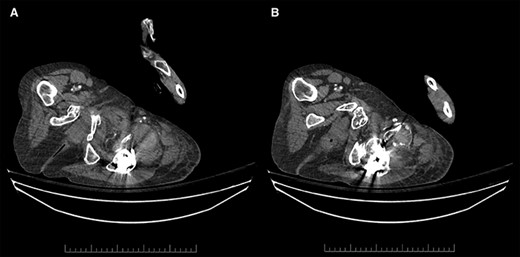

Unfortunately, due to increasing pain and difficulty weight-bearing, she presented to the emergency room on POD33. She was found to have new left thigh swelling and pain. Deep vein thrombosis (DVT) was ruled out with duplex ultrasound; however, a large left DFA pseudoaneurysm measuring 5.6 cm in length with a neck of 0.4 cm was visualized (Fig. 2). Computed tomography (CT) imaging confirmed a left DFA branch pseudoaneurysm with active extravasation, adjacent to a free-floating osseous fragment, associated with a large thigh hematoma (Fig. 3). In consultation with hematology, her apixaban was not reversed.

Contrast-enhanced arterial phase axial computed tomographic (CT) images overlying the left hip demonstrating (A) hyperdense material anterior to the left hip in keeping with hematoma (left), and (B) hyperdense material that corresponds to the pseudoaneurysm, which is supplied by a small DFA branch coursing anteriorly and abutting a sharp osseous fragment (right).